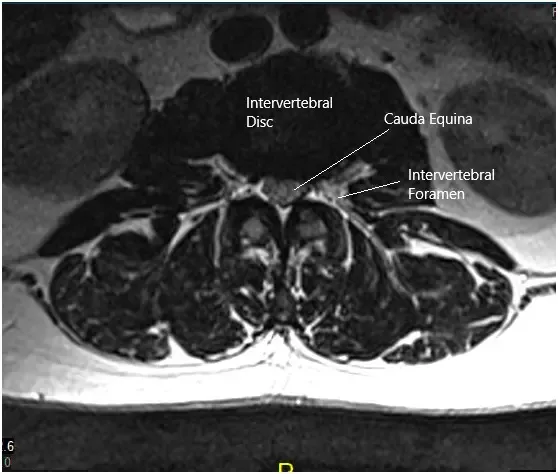

MRI of the lumbosacral spine in sagittal and axial views.

A 50-year-old male patient who started experiencing excruciating pain down his left leg with weakness in that leg and numbness in his peroneal region. His sensory deficit included his lateral thigh and entire foot as well. He obtained an MRI that showed a disk fragment compressing on the L5 and S1 nerve roots with severe lumbar stenosis in the lateral recess and encroachment on the left side at L5 and S1.

Grade I anterolisthesis of L2 on L3. Straightening of the lumbar lordosis. Degenerative changes are identified diffusely within the lumbar spine. At L5-S1, there is a left-sided disc herniation/protrusion causing mild narrowing of the thecal sac and narrowing of the left lateral recess. This encroaches upon the left S1 nerve root within the left lateral recess.

The hernia also extends into the proximal left neural foramen causing mild narrowing. The mild right neural foraminal narrowing is also visualized. Mild to moderate narrowing of the thecal sac is identified at L2-3.